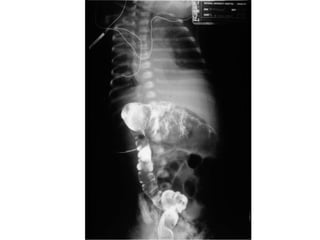

Syndrome occlusif chez un

nourrisson avec hernie étranglée

depuis 24h

Occlusion du grêle:

niveaux hydroaériques

centraux, plus larges que

hauts, absence d’air dans

le rectum

Occlusion colique

Niveaux hydroaériques périphériques, plus hauts que larges